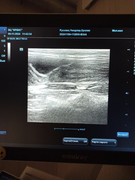

Сделали повторное узи 22.11. 2024 (первое было 09.11.2024). Высылаю фото и заключение.

Теперь ставят гидрометру и эндометрит. По мочевому мочекаменную.